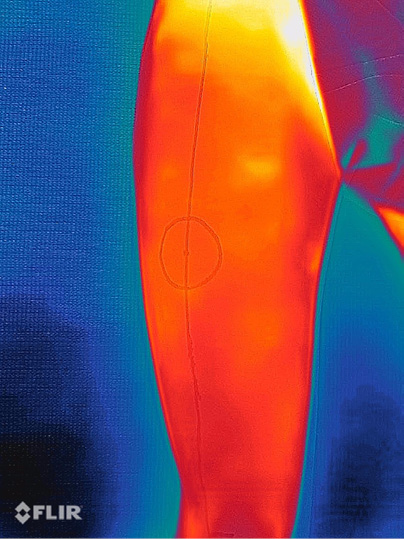

Tiriamiesiems nupieštas ALT lopas priekiniame ir šoniniame šlaunies paviršiuje: nubrėžta tiesė, jungianti priekinį viršutinį klubakaulio dyglį (ASIS) su šoniniu viršutiniu girnelės kraštu. Žymikliu pažymėtas taškas, dalijantis tiesę į dvi lygias dalis. Nuo šio taško nubrėžtas 5 cm skersmens apskritimas, kuriame ieškota odą maitinančios perforantės (1 pav.). Prieš tiriant termovizoriumi, tiriamoji sritis atvėsinta įprastu chirurginiu antiseptiku, jį užpurškiant ant šlaunų priekinių ir šoninių paviršių odos („šalčio iššūkis“) (2–3 pav.). Antiseptikui nudžiūvus, praėjus 2 min., kambario temperatūroje (22 °C) buvo atliekamos dinaminės termogramos termovizoriumi (FLIR One PRO®; FLIR Systems Inc., Wilsonwille, Ore.), raudonu žymikliu ant odos pažymėti „karšti taškai“, tiriamojo anketoje pažymėtas nustatytas „karštų taškų“ skaičius ir šių taškų atstumas nuo priekinio viršutinio klubakaulio dyglio (4 pav.).

3 pav. Tiriamosios srities termograma po „šalčio iššūkio“

4 pav. Termograma, užfiksuota praėjus 2 min. po „šalčio iššūkio“ (pastebimas vienas „karštas taškas“ ties apatine tiriamosios zonos riba)